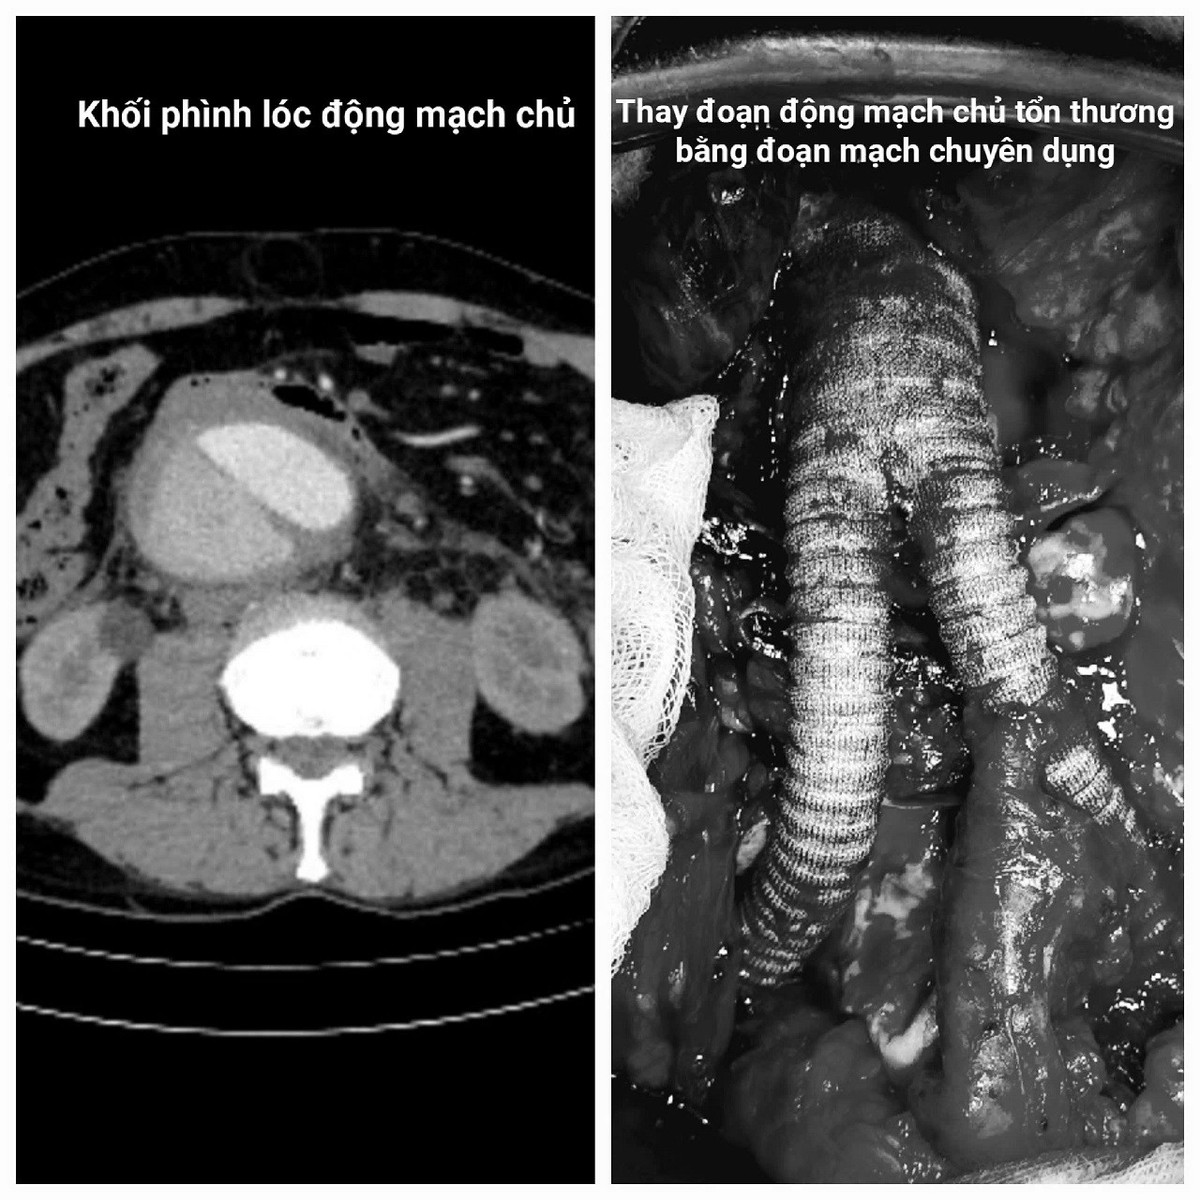

Hàng loạt xét nghiệm chuyên sâu, đặc biệt là chụp cắt lớp vi tính (CT) đã phát hiện thảm kịch kép: Không chỉ lóc tách phức tạp, ông Janusz còn mang trong bụng một "quả bom nổ chậm" - khối phình động mạch chủ bụng khổng lồ, đường kính lên tới 9cm (gấp 3 lần bình thường), đang có dấu hiệu vỡ, máu tụ sau phúc mạc.

"Đây là tình trạng cực kỳ nguy hiểm. Người bệnh có thể tử vong tức thì do sốc mất máu ồ ạt nếu khối phình vỡ hoàn toàn. Chỉ định phẫu thuật cấp cứu thay đoạn động mạch chủ bị tổn thương là bắt buộc để giành giật sự sống", TS.BS. Ngô Gia Khánh - Trưởng khoa Phẫu thuật Lồng ngực & Mạch máu nhấn mạnh.

Tiếp theo là quá trình thay thế hoàn hảo đoạn động mạch chủ - chậu bị tổn thương bằng một đoạn mạch máu nhân tạo. Từng đường khâu nối mạch máu tỉ mẩn, chính xác dưới kính vi phẫu.